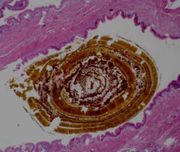

Mikroskopische Aufnahme eines Cholesterinpigmentsteines.